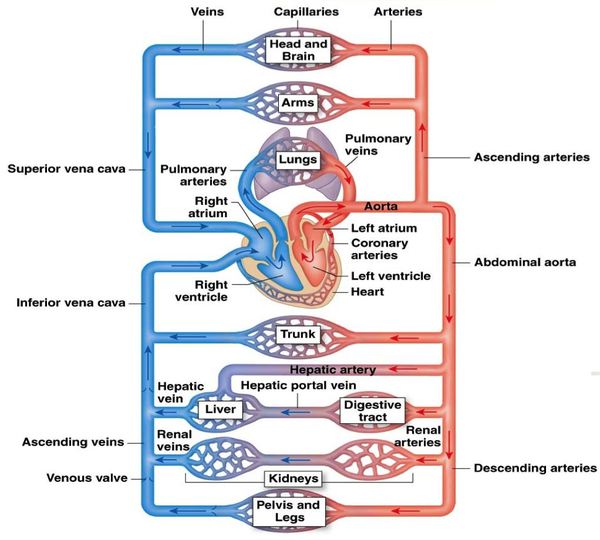

Cardiovascular physiology is the study of the cardiovascular system, specifically addressing the physiology of the heart (cardiac physiology) and blood vessels (circulatory physiologic) (see figure 16[95]). The cardiovascular system is a pressurized closed system responsible for transporting nutrients, hormones, and cellular waste throughout the body. From a physical point of view, there are three independent circuits:

- Systemic Circulation: The former brings oxygenated blood from the heart, thought arteries and capillaries, to the various organs (systemic arterial system) and then brings it back to heart (systemic venous system). The systemic arterial system is an extensive high-pressure system; hence the structure of its blood vessels reflects the high pressures to which they are subjected. The systemic venous system acts as a collecting system, returning blood from the capillary networks to the heart passively down a pressure gradient.

- Pulmonary circulation: The latter pumps the venous blood into the pulmonary artery where it enters the pulmonary system, through the pulmonary veins, get oxygenated and is finally received by the heart, ready to be sent to the systemic circulation (where the blood is pumped through the aortic valve into the aorta).

- The coronary circulation arises from the aorta and provides a blood supply to the myocardium, the heart muscle

This monograph will focus on systemic arterial system and coronary circulation.